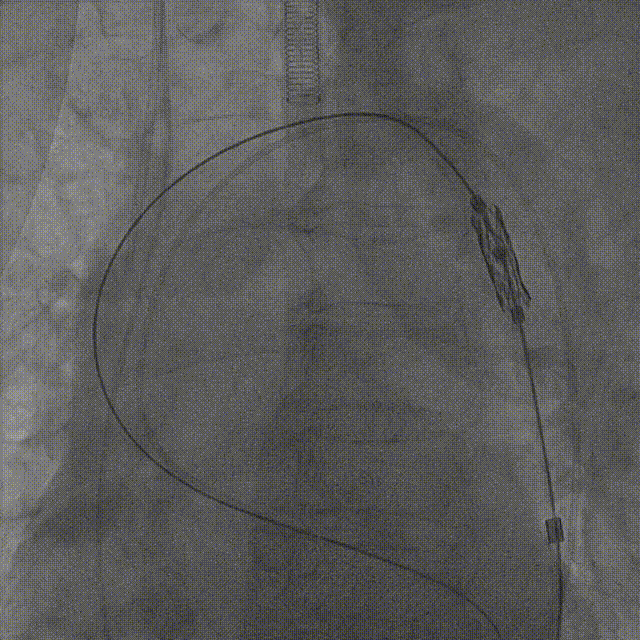

患者取平卧位,常规消毒铺巾,穿刺右侧颈内静脉,置入临时起搏器;穿刺左股动脉置入6F鞘,沿鞘管送入猪尾导管,然后再穿刺右股动脉预置两把Proglid血管缝合器,然后置入14F鞘管;主动脉根部造影显示主动脉瓣钙化粘连,开放严重受限;直泥鳅钢丝跨瓣导丝到左室,左心室及升主动脉测压,峰值跨瓣压差高达127mmHg;

交换为预塑性的加硬钢丝至左心室,然后送入预装有Myval™ 20mm瓣膜的输送系统,成功完成跨瓣操作到达主动脉根部,调整瓣膜深度;

参考术前CT测量值,调整瓣膜至释放前最佳高度,缓慢释放近1/3长度时复查主动脉根部造影,确认瓣膜高度适合,临时起搏180次/分,以80:20比例13mL快速释放瓣膜至瓣膜工作区完全打开,于标准位置释放瓣膜;

复查造影提示瓣膜固定良好,形态可,仅少量反流;复查超声提示瓣膜功能正常,平均跨瓣压差下降为11mmHg,未见明显瓣周漏;最后退出鞘管,缝合血管。